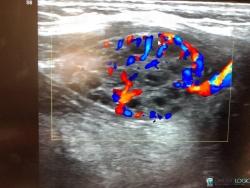

18 yr old for USG neck- Altered thyroid funtion See more

Lingual thyroid( ectopic thyroid) with secondary colloid goiter changes See more